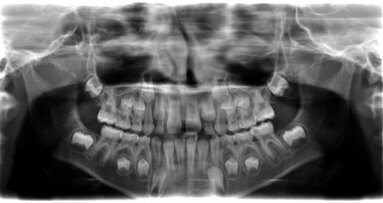

Une analyse cone beam iCAT a été effectuée pour évaluer l'os autour de la dent, avant l'extraction et la pose de l'implant. Du modèle de diagnostic, nous avons élaboré une clé pour la restauration provisoire.

Un implant Astra, 4.0 x 13 mm, a été utilisé, dans ce cas. Après l'implantation, un pilier provisoire a été placé est préparé, à l'extérieur de la bouche, à la marge gingivale. Le matériau provisoire Luxatemp a été utilisé pour fabriquer la couronne temporaire.

Les empreintes ont été envoyées à notre prothésiste, qui a coulé le modèle avec l'analogue de l'implant et l'a envoyé à Atlantis pour une fabrication correcte. Dans ce cas, un épaulement anatomique en zircone a été prescrit, à 1 mm sous la gencive en vestibulaire et à 0.75 en palatin.